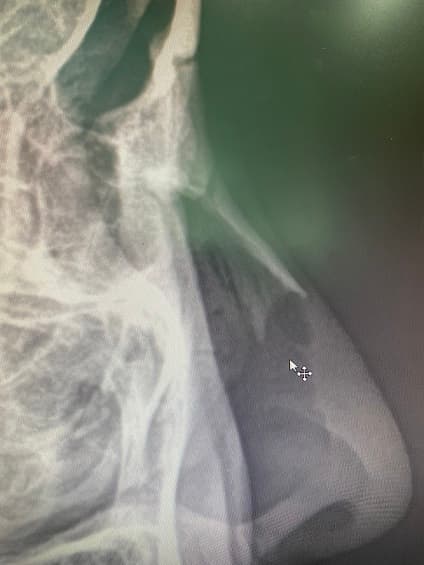

몇 일 전에 찍은 코 엑스레이 사진인데요.

코 엑스레이에 대해 궁금하시군요. 붉은색으로 표시하신 부분은 코에 존재하는 연골입니다. 뼈보다는 덜 하얗게 보이지만 분명 그 윤곽을 확인할 수 있습니다.

해당부분은 연골로 칼슘등이 있고 이또한 고체성분이기 때문에 뼈보다는 옅은 흰색으로 보일 수 있습니다